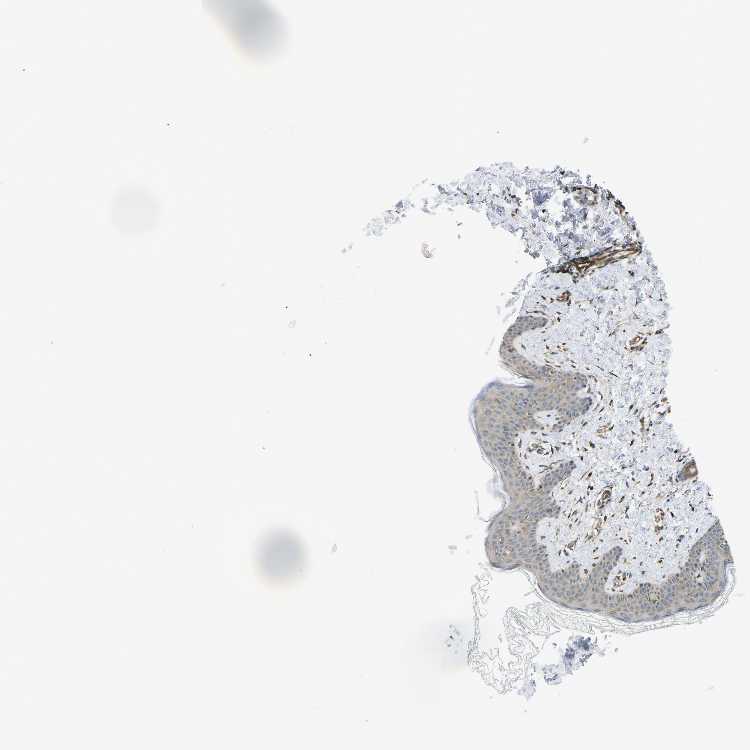

SKIN 1 - Antibody stainingi

Antibody staining in the annotated cell types in the current human tissue is reported as not detected, low, medium, or high, based on conventional immunohistochemistry profiling in selected tissues. This score is based on the combination of the staining intensity and fraction of stained cells.

Each image is clickable and will lead to virtual microscopy that enables deeper exploration of all samples and also displays staining intensity scores, fraction scores and subcellular localization as well as patient and tissue information for each sample.

Antibody HPA015716

Langerhans Low

Fibroblasts High

Keratinocytes Low

Melanocytes Low